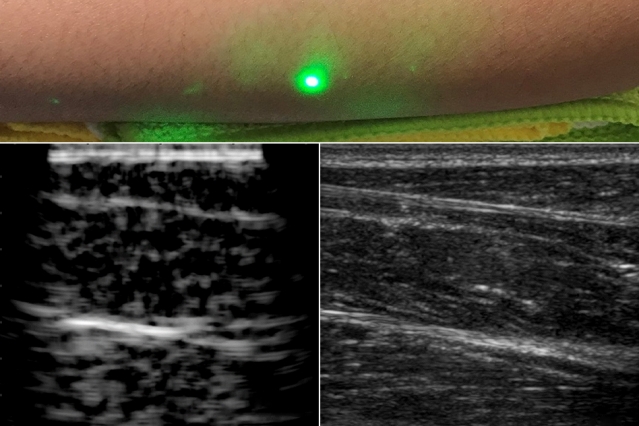

.

@MIT engineers including@MIT_IMES researcher Brian Anthony (Principal Research Scientist@MITMechE) devise new ultrasound technique that doesn’t require contact with body to see inside a patient#MITnano https://bit.ly/2FkiKoW pic.twitter.com/HMSEzTQuLh